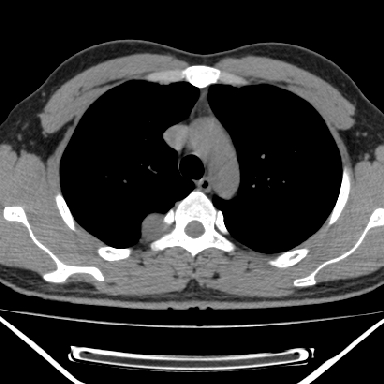

右上后纵隔脊柱旁类圆形肿块,边界光整,与胸腔呈钝角,首先考虑来源于肺外,神经源性肿瘤(神经鞘瘤可能大,神经鞘瘤)

右上后纵隔旁软组织肿块影,与肺界面光滑,与胸壁呈钝角相交,提示肺外病变。位于肋骨下缘,边缘清楚,呈三角样指向与右侧椎间孔,但并示进入椎间孔;与对侧神经根对比,属同一走行方向。

右上后纵隔脊柱旁类圆形肿块,边界光整,与胸腔呈钝角,首先考虑来源于纵膈,神经源性肿瘤可能大。

右上后纵隔脊柱旁见长椭圆形肿块,边界光整,与胸壁呈钝角。周围骨质未见异常。

右上后纵隔脊柱旁类圆形肿块,边界光整,与胸膜呈钝角,首先考虑来源于肺外,神经源性肿瘤(神经纤维瘤可能大)。